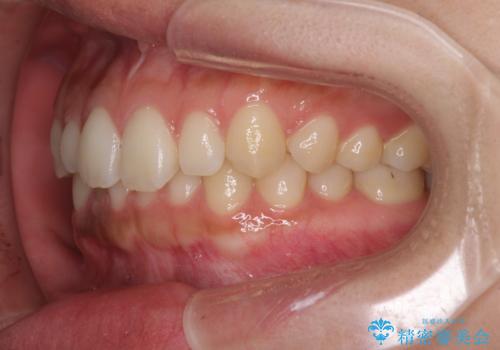

海外勤務中でも矯正治療 インビザラインによる軽度叢生改善

- 前歯のデコボコを気にして来院された患者様です。

治療期間中に海外勤務になる可能性が高いことが分かっていましたが、矯正治療を始めたいとのことでしたので、インビザラインを用いて治療することとしました。

通常であれば半年から10ヶ月程度で終了する歯並びでしたが、海外に長期出張することになったため、1年10ヶ月の期間を要しました。

出張に行かれてしまうと追加のマウスピースを発注できないため、マウスピースの交換頻度を低くし、一時帰国のタイミングに合わせていくことで、スムーズに進めて行くことができました。